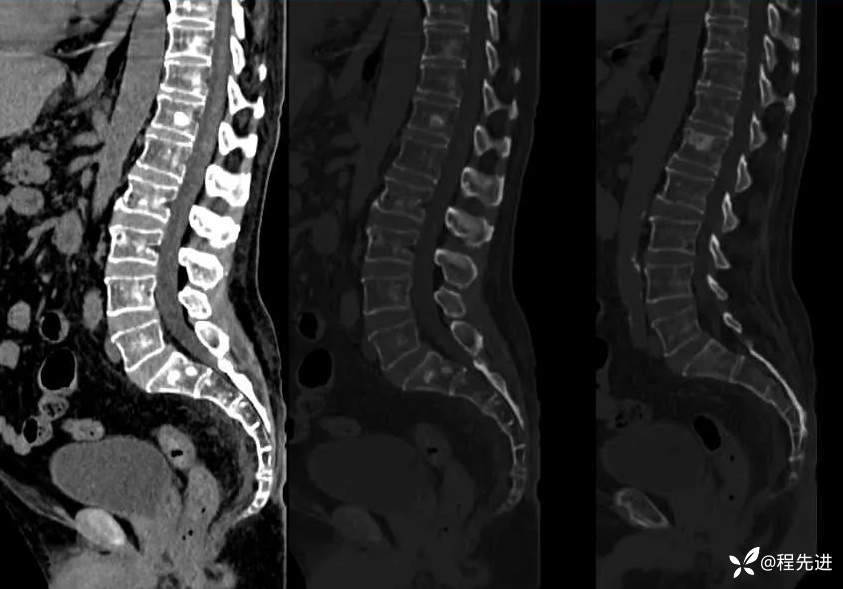

腰椎: